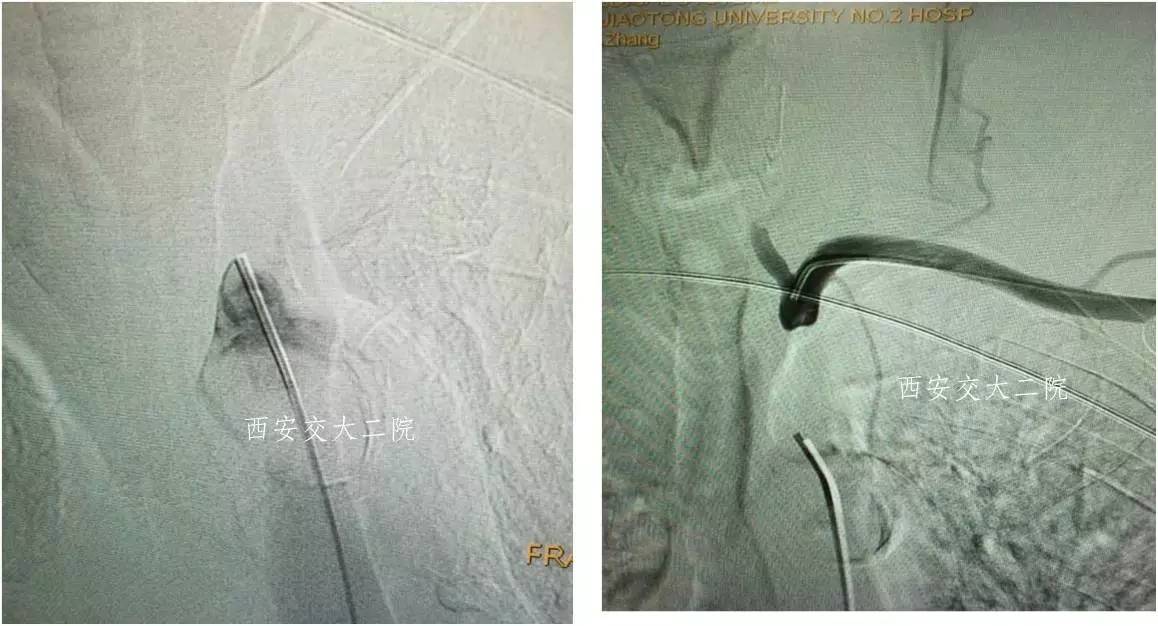

Case 4 颈内动脉颅内段闭塞再通术

》女,57岁;

》左侧肢体无力1月于2014.1.8入院;

》诊断:脑梗死(右侧半卵圆中心)。

术前脑CT

术后患者病情逐渐好转。

术后3月自动停药,1年后再发右侧颈内动脉供血区脑梗,复查DSA见再通支架处血管再次闭塞。